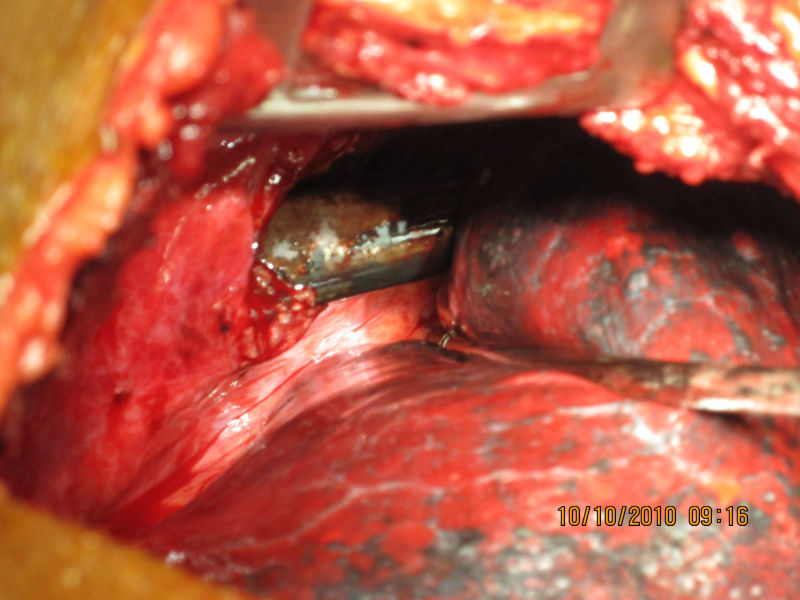

Aortic Dissection + CABG

A 58 year old patient who had renal transplant 25 years earlier developed Aortic Dissection and Coronary Artery disease. He underwent successful Bentall's operation (replacement of aortic valve and ascending aorta and reimplantation of coronary arteries) with CABG (3 grafts). He did not require renal dialysis throughout his stay in the hospital and was discharged with normal renal function.